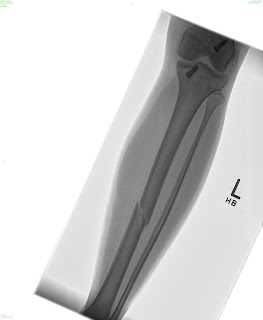

Sorry that I have been MIA for so long! I actually broke my leg on August 9th… I fractured my tibia (the big weight bearing bone in your shin) all the way through. I had the option to be in a full length cast (from my hip to my toes) for 8 weeks, or to have surgery and a rod placed so that I can walk on my leg. I chose to have surgery and now I am just going through recovery. I am working on teaching myself how to walk normal with that leg again. I am happy to be up and moving and not in a cast, but its definitely not a fun process. I have new crafts to put up soon! Some darling candy corns and a pumpkin set for the porch! I will work on getting those posted as soon as I can.

Here are some awesome pictures of my broken leg!